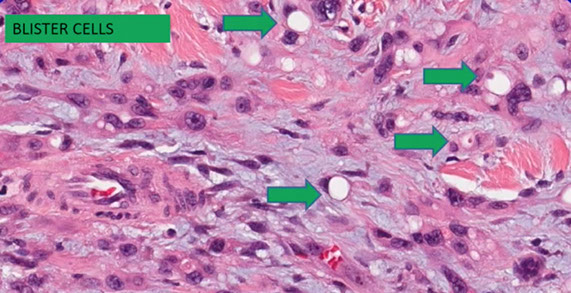

Micro: cords / small nests of round endothelial cells c lots of reddish cytoplasm that expand the vessels as they extend centrifugally from the lumen to the soft tissue in myxoid / mucinous sclerotic background

- blister cells c red cell fragments, which are tumor cells trying to form vascular lumens (similar to what may be seen in lobular breast ca)

-- can have vacuoles in lots of vascular tumors (blister cells are NOT specific for EHE) with plump endothelial cells